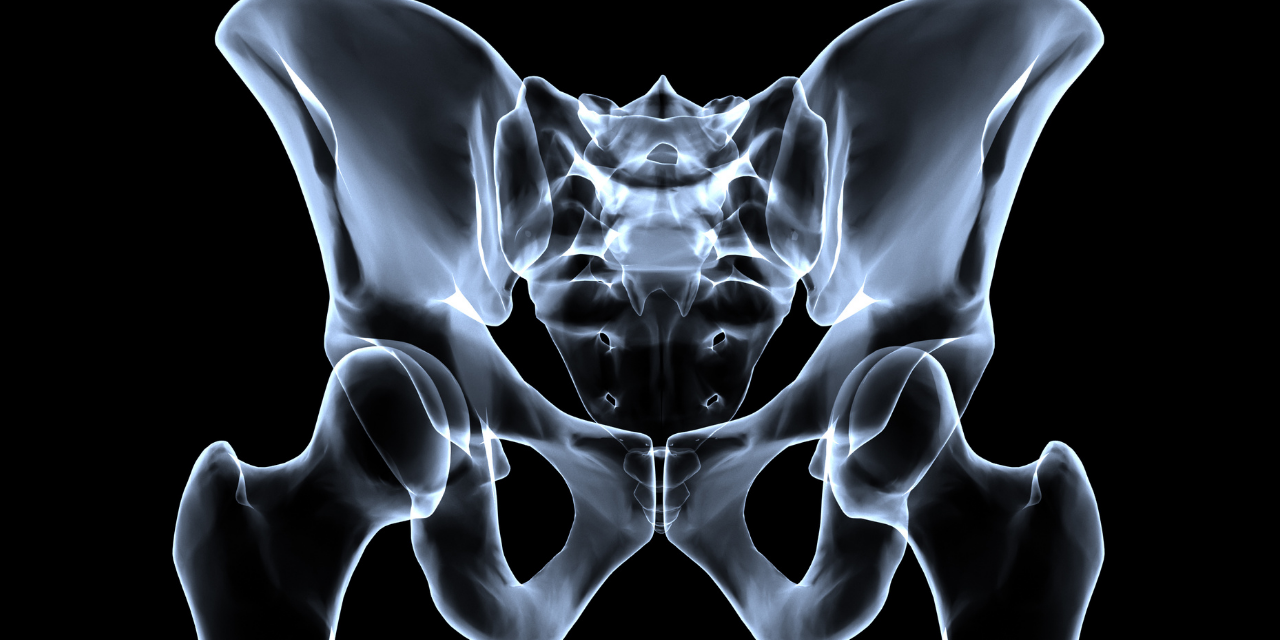

The pelvic floor is one of the body’s most complex anatomical and functional regions. (1) It serves to enclose the bony pelvic outlet and support the pelvic viscera while allowing controlled outlets for the rectum, urethra, and vagina. (2) Dysfunction of the pelvic floor muscles can produce a range of symptoms, including pain, incontinence, urgency, sexual dysfunction, and organ prolapse. Pelvic floor dysfunction is a frequently overlooked or ignored problem that significantly impacts personal, social, and work activities, mental well-being, and quality of life. (3-5)

The 3 Layers

The pelvic floor can be divided into three layers. (6) The internal layer consists of the peritoneum of the pelvic viscera. The external layer includes the skin of the vulva, scrotum, and perineum. The more robust middle layer comprises the endopelvic fascia and several muscles, including the urogenital sphincter, external anal sphincter, ischiocavernosus, bulbospongiosus, transverse perineal muscles, and levator ani group (pubococcygeus muscle, puborectalis, and iliococcygeus). (6,7) The hammock-shaped pelvic floor muscles attach anteriorly to the symphysis pubis and posteriorly to the coccyx. (7)

In addition to supporting the intestines, urinary bladder, and uterus, the pelvic floor muscles also function in unison to maintain bowel, bladder, and sexual function. (8-10) Voluntary contraction of the pelvic floor muscles lifts the pelvic contents and tightens orifices. (7) During pregnancy, the pelvic floor muscles support the developing fetus and assist with natural delivery. (8,11) Contraction of the sphincter muscles controls the release of the urine, feces, and gas, while relaxation (or the inability to maintain contraction) permits passage. (2,8,10) The pelvic floor muscles also play a significant role in sexual sensation and function for both genders. (10-13)

The pelvic floor contributes substantially to core stability. (71) Coordinated contraction of the pelvic floor muscles is necessary to pressurize the abdominal canister and generate spinal stability. (Please see the Chiro Up Spinal Instability Protocol for a more comprehensive explanation.)